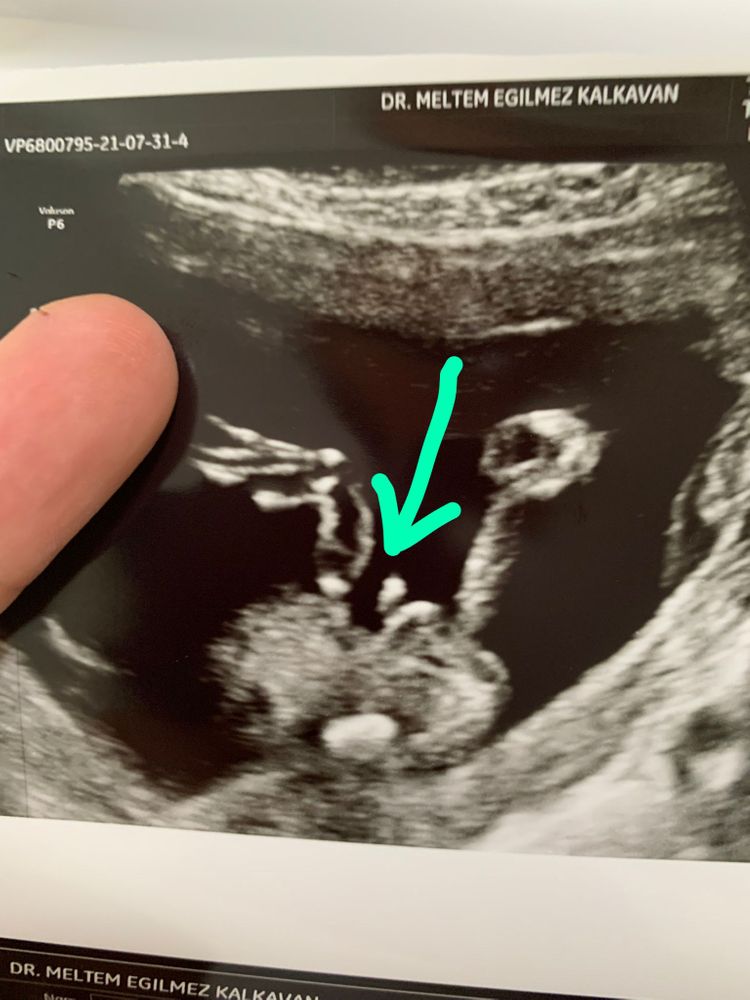

Сегодня были наконец-то на узи🤗😍🤪😊

У нас точно мальчик

По развитию опережает на неделю.

Я так рада. Что ребеночек здоров, что все в порядке с ним. Показывала 3Д) такой хорошенький. Прям человечек.

Лежит себе на спине, глазки трет.